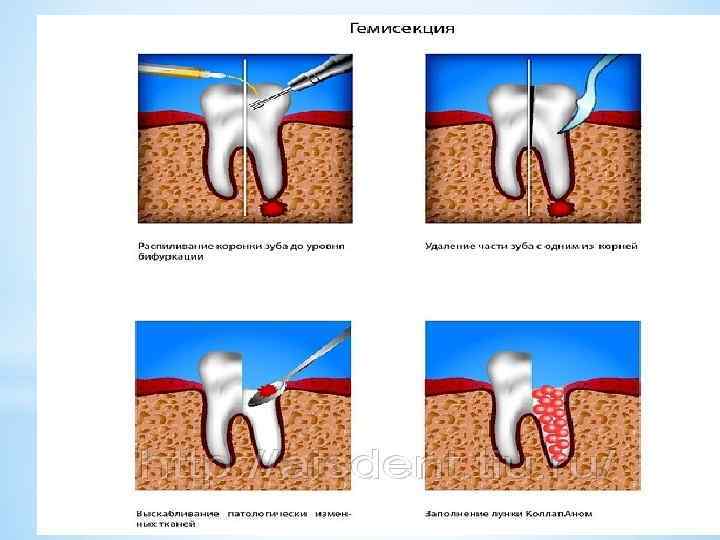

При гемисекции зуба под местной анестезией проводится вертикальное рассечение многокорневого зуба с последующим удалением той части, в области верхушки корня которой имеется хронический очаг инфекции. Перед операцией гемисекции хирург пломбирует каналы корней зубов, подлежащие сохранению. Иногда при гемисекции врачу приходится отслаивать слизистонадкостничный лоскут, после чего с помощью бормашины удаляется поврежденный корень. Зуб после гемисекции полностью сохраняет свою функциональность и может быть использован для установления ортопедических конструкций.

При гемисекции зуба под местной анестезией проводится вертикальное рассечение многокорневого зуба с последующим удалением той части, в области верхушки корня которой имеется хронический очаг инфекции. Перед операцией гемисекции хирург пломбирует каналы корней зубов, подлежащие сохранению. Иногда при гемисекции врачу приходится отслаивать слизистонадкостничный лоскут, после чего с помощью бормашины удаляется поврежденный корень. Зуб после гемисекции полностью сохраняет свою функциональность и может быть использован для установления ортопедических конструкций.

*Возможно два варианта проведения операции гемисекции. *В первом случае принцип хода операции следующий. Производится сепарация коронки, то есть коронку распиливают до области бифуркации (места разделения на корни), после чего происходит удаление корня. *Другой вариант – лоскутный метод. Хирург отслаивает слизисто-надкостничный лоскут, после чего вырезает причинный корень. Освободившуюся полость заполняют веществом, способствующим заживлению тканей. Лоскут возвращается на место и ушивается. *

*Возможно два варианта проведения операции гемисекции. *В первом случае принцип хода операции следующий. Производится сепарация коронки, то есть коронку распиливают до области бифуркации (места разделения на корни), после чего происходит удаление корня. *Другой вариант – лоскутный метод. Хирург отслаивает слизисто-надкостничный лоскут, после чего вырезает причинный корень. Освободившуюся полость заполняют веществом, способствующим заживлению тканей. Лоскут возвращается на место и ушивается. *

*-Алгоритм проведения: выбор анестетика; - выбор нужных инструментов; - подготовка бормашины и наконечника к операции; - обработка рук; - проведение анестезии; - разрез слизистой, надкостницы в проекции корней зуба; - отслоение слизисто-надкостничного лоскута, оголение кости альвеолярного отростка; - снятие бором кости над корнем, который удаляется; - проведение бором, диском сепарации коронки зуба; - удаление пораженной части зуба (половина коронки и корень); - нивелирование острых костных краев; - удаление кюретожной ложкой грануляций; - обработка раны 3% р-ром Н 202, высушивание; - укладывание лоскута на место; - накладывание швов.

*-Алгоритм проведения: выбор анестетика; - выбор нужных инструментов; - подготовка бормашины и наконечника к операции; - обработка рук; - проведение анестезии; - разрез слизистой, надкостницы в проекции корней зуба; - отслоение слизисто-надкостничного лоскута, оголение кости альвеолярного отростка; - снятие бором кости над корнем, который удаляется; - проведение бором, диском сепарации коронки зуба; - удаление пораженной части зуба (половина коронки и корень); - нивелирование острых костных краев; - удаление кюретожной ложкой грануляций; - обработка раны 3% р-ром Н 202, высушивание; - укладывание лоскута на место; - накладывание швов.